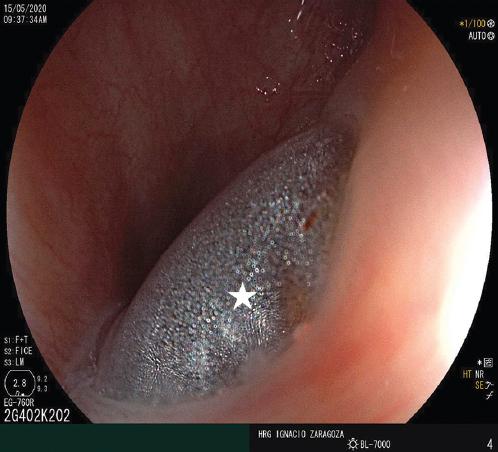

Figura 1 Imagen endoscópica en la que se observa la protrusión del balón (señalada con una estrella) del tubo endotraqueal hacia la luz esofágica.

La fístula traqueoesofágica debe sospecharse clínicamente si se presentan una distensión masiva del abdomen, secreciones anómalas o aspiración de contenido gastroalimentario desde el árbol traqueobronquial. La confirmación de la sospecha clínica puede realizarse mediante endoscopia superior, en la que se observa el balón endotraqueal protruyendo hacia la luz esofágica a través del trayecto fistuloso. La broncoscopia con fibra óptica debe efectuarse para definir el sitio exacto y las dimensiones de la fístula, así como para evidenciar estenosis laríngea o traqueal concomitante10,11.